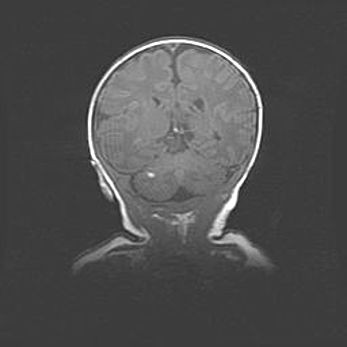

Церебральная ишемия II.

Возраст: 5 дней

Вес: 3400 г

Пол: женский

Окружность головы: 35 см

Срок гестации: 39 недель

Церебральная ишемия – это заболевание, характеризующееся недостаточностью (гипоксией) либо полным прекращением (аноксией) снабжения мозга кислородом по причине закупорки одного или нескольких сосудов. Это приводит к  что метаболическим расстройствам различной степени тяжести в тканях головного мозга, развитию коагуляционных некрозов и гибели нейронов.